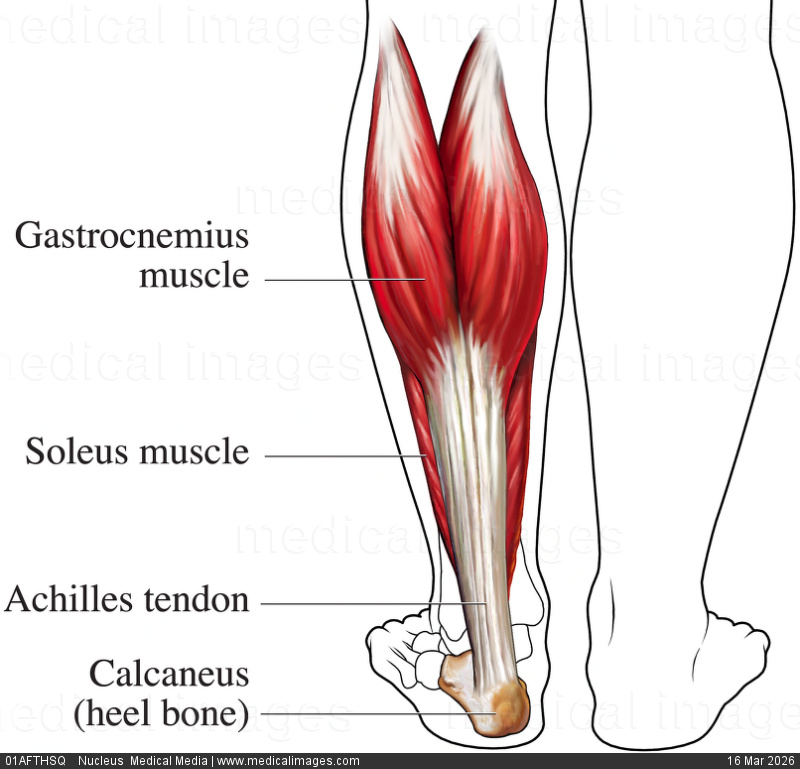

Anatomy and Biomechanics of the Achilles Tendon

The Achilles tendon is the most robust tendon in the body, formed by the confluence of the medial gastrocnemius, lateral gastrocnemius, and soleus tendons (triceps surae musculotendinous complex). It inserts onto the posterosuperior aspect of the calcaneus after a 90° counterclockwise rotation on its longitudinal axis. This intrinsic torsion generates a hypovascular zone between 2 and 6 cm proximal to the calcaneal insertion — the critical zone — where the majority of degenerative ruptures occur.